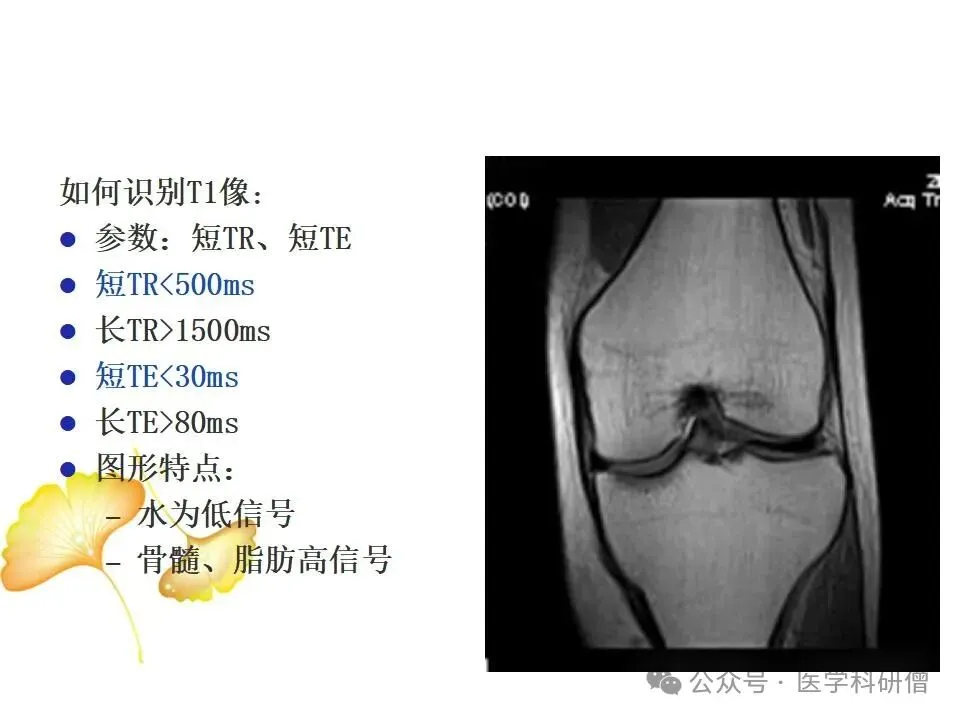

• T1加权像:能够清晰显示韧带的解剖结构,帮助医生观察韧带是否完整、是否有撕裂的迹象。